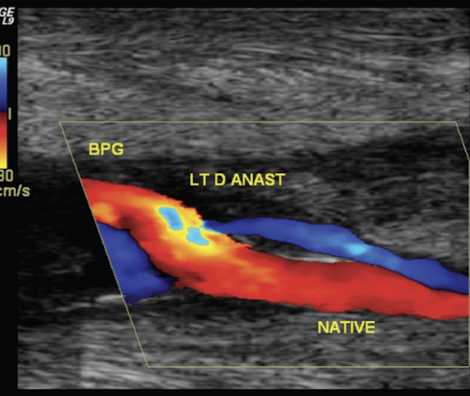

Color flow imaging of grafts

indicates mild changes in flow profiles

aliasing in stenosis